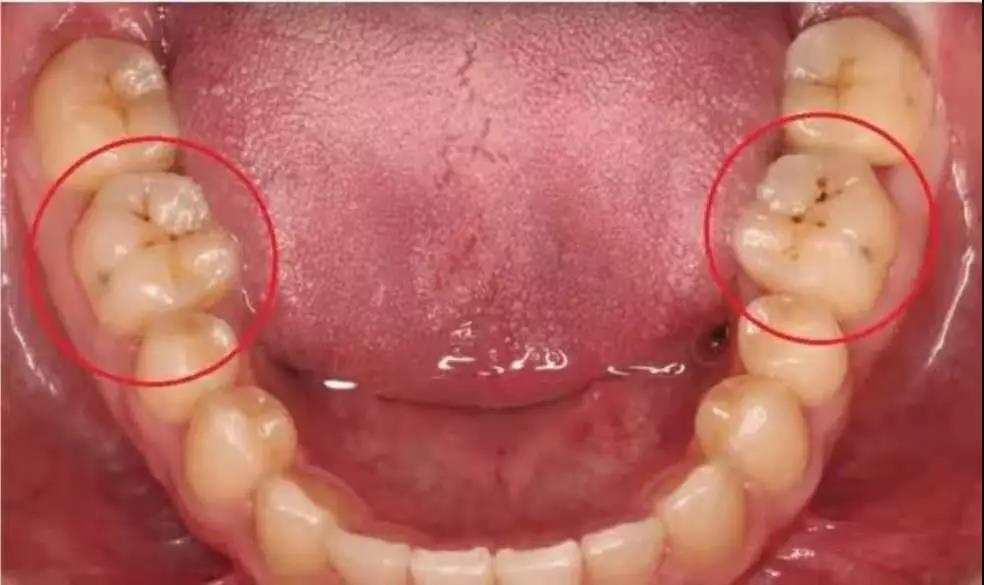

1、智齿发炎怎么治疗 1.1、双氧水+盐水,交替漱口 对于轻度的智齿发炎,可以先用双氧水漱口。不过需要记住的是:双氧水要加两倍的水,不要用原液。然后再用盐水漱口,每天多漱口...